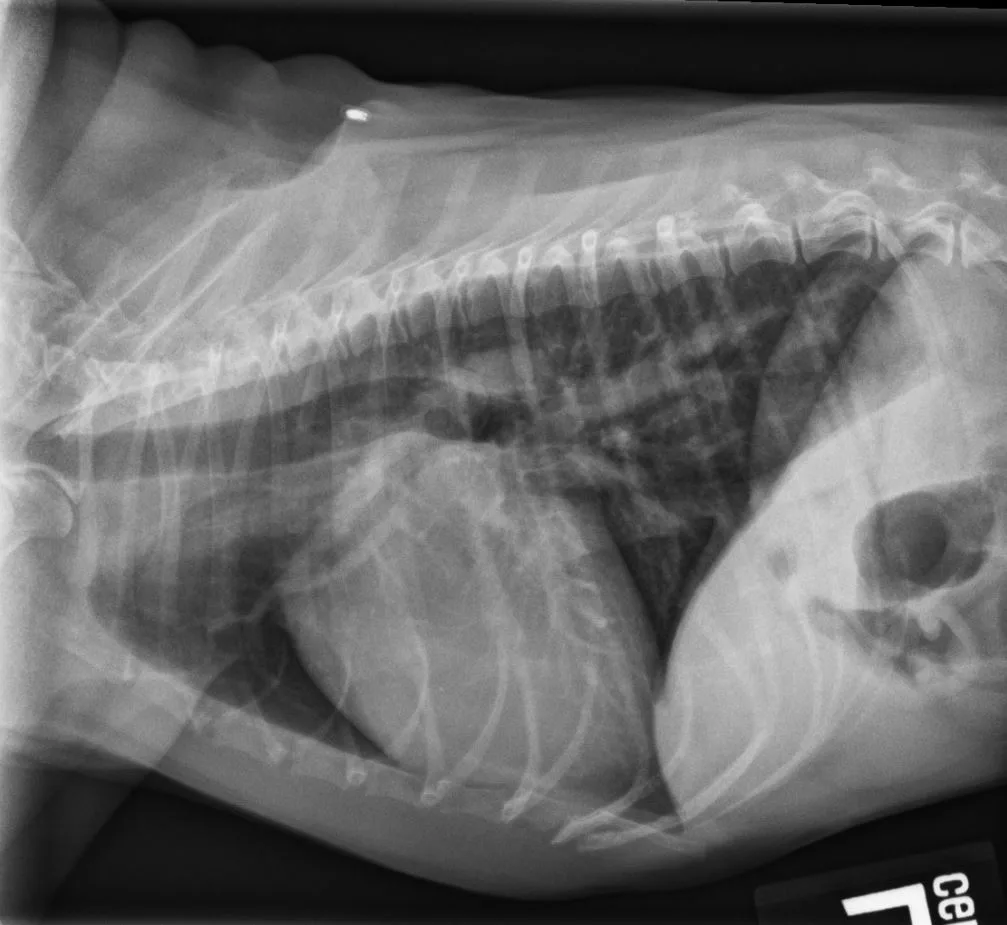

Vertebral heart scale (VHS) is widely used in clinical practice as an objective method to assess cardiac size and is relatively simple to determine at initial and follow-up examinations; however, it can be difficult to determine VHS in patients with vertebral alterations, which can artifactually increase VHS.1,2

Authors of this study hypothesized that a single vertebra retains its proportion with respect to the whole body as well as the thoracic vertebral tract and using a single vertebra without shape and dimension alterations might allow objective evaluation of cardiac silhouette dimensions, even in the presence of thoracic spine alterations. The authors thus sought to create a novel method, heart:single vertebra ratio (HSVR), for radiographic evaluation of cardiac silhouette size. Length of each vertebral body from the fourth to eighth thoracic vertebrae, including respective caudal intervertebral space, was measured, as well as the cardiac long and short axes. HSVR was calculated by dividing the sum of the cardiac long and short axes by the length of each vertebral body. Radiographs of 80 dogs were included in the final assessment.

Substantial agreement was seen between VHS and HSVR determined using the seventh thoracic vertebra (HSVRT7). Results also indicated that when determining HSVRT7 is not possible, ratios using other vertebrae can be used in the following order of preference: HSVRT8, HSVRT5, and HSVRT6; however, these ratios showed slightly lower agreement with VHS compared with HSVRT7. Using the fourth thoracic vertebra (HSVRT4) was least favorable due to its lower, although still acceptable, agreement with VHS. Good to excellent inter- and intraobserver agreement for HSVR was noted.

The authors concluded that determining HSVR can overcome the intrinsic limitation of using VHS in patients with spinal alterations, including alterations that involve thoracic vertebrae between T4 and T8, representing a more objective evaluation of cardiac silhouette dimensions.